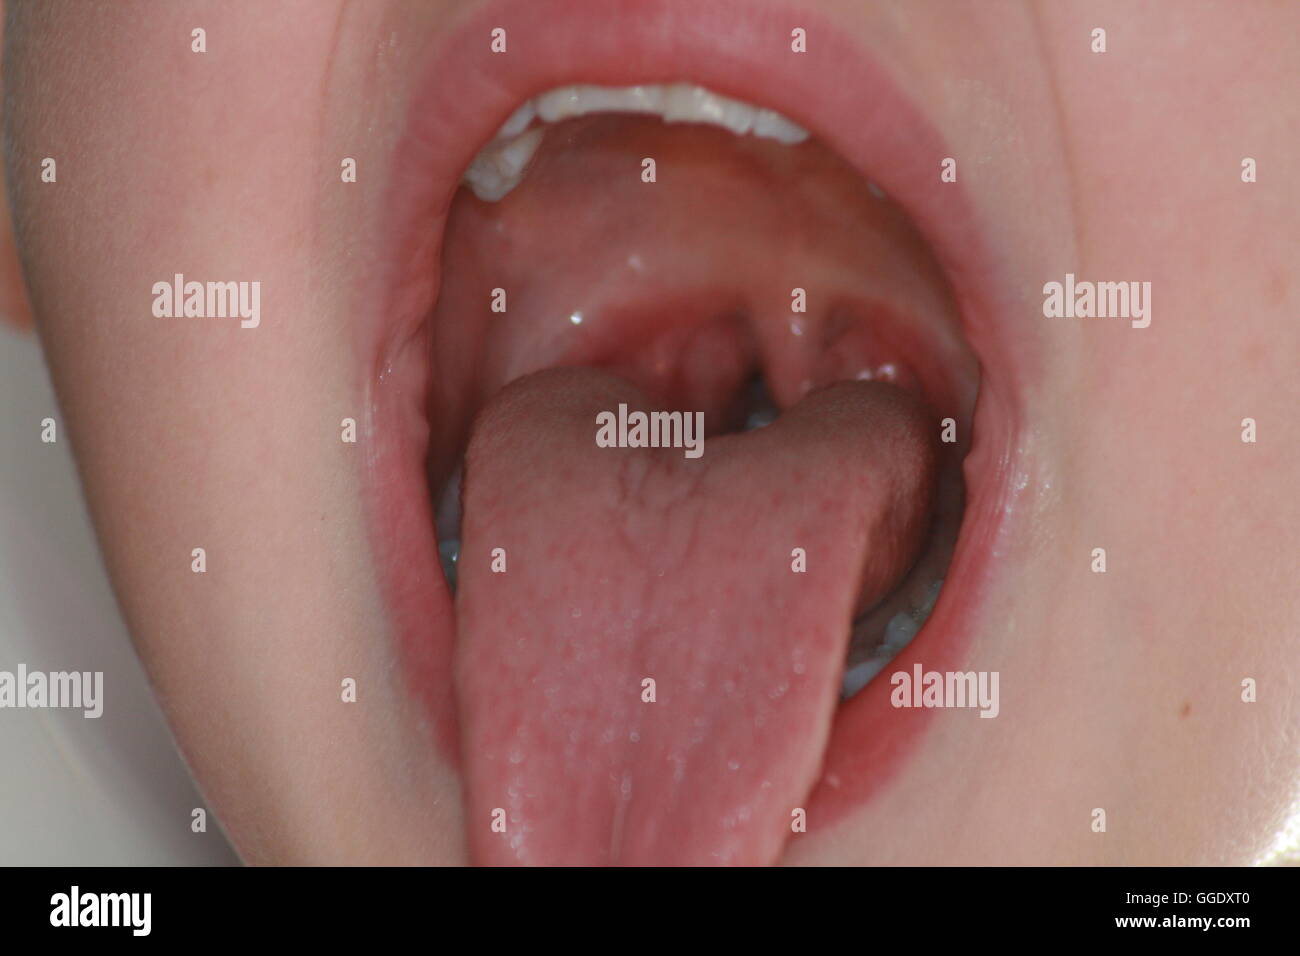

Childs offener Mund mit Blick auf Mandeln Stockfotohttps://www.alamy.de/image-license-details/?v=1https://www.alamy.de/stockfoto-childs-offener-mund-mit-blick-auf-mandeln-113403136.html

Childs offener Mund mit Blick auf Mandeln Stockfotohttps://www.alamy.de/image-license-details/?v=1https://www.alamy.de/stockfoto-childs-offener-mund-mit-blick-auf-mandeln-113403136.htmlRFGGDXT0–Childs offener Mund mit Blick auf Mandeln